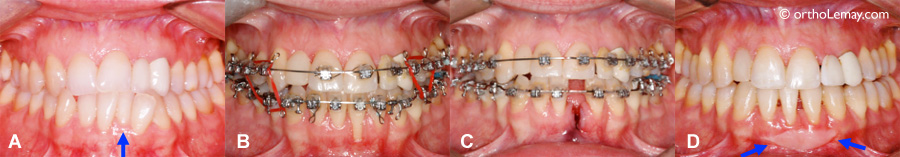

(A) Avant le traitement, l’incisive inférieure gauche est basculée à l’intérieur de l’arcade dentaire (flèche) . À cause du déséquilibre squelettique entre les mâchoires et l’étroitesse de l’arcade, l’alignement de cette incisive la déplacera vers l’avant. (B) L’alignement a causé une perte importante de gencive et d’os alvéolaire qui supportent la dent (récession/déchaussement). (C) Il fut alors décidé d’extraire l’incisive et de fermer l’espace en orthodontie. (D) Résultat final à la fin de l’orthodontie. Une greffe gingivale fut faite (flèches) pour améliorer la qualité de la gencive restante devant les autres incisives.